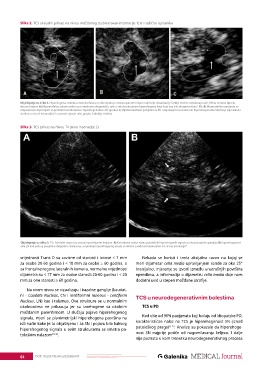

Slika 3. TCS prikaz na nivou TV (nivo insonacije 2)

Objašnjenje uz sliku 3. TV i frontalni rogovi su ocrtani isprekidanim linijama. A) Kod zdrave osobe nema patoloških hiperehogenih signala u nivou bazalnih ganglija; B) hiperehogenost

oba LN kod jednog pacijenta obilježeno strelicama, a mjerenje hiperehogenog areala se obično izvodi kontralateralno od strane insonacije 4